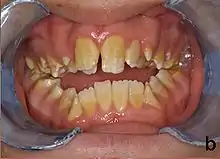

Amelogenesis imperfecta, hypoplastic type. Note the association of pitted enamel and open bite.

People with amelogenesis imperfecta may have teeth with abnormal color: yellow, brown or grey; this disorder can affect any number of teeth of both dentitions. Enamel hypoplasia manifests in a variety of ways depending on the type of AI an individual has (see below), with pitting and plane-form defects common.[4] The teeth have a higher risk for dental cavities and are hypersensitive to temperature changes as well as rapid attrition, excessive calculus deposition, and gingival hyperplasia.[5] The earliest known case of AI is in an extinct hominid species called Paranthropus robustus, with over a third of individuals displaying this condition.[6]

Type 1 - Hypoplastic

Enamel of abnormal thickness due to malfunction in enamel matrix formation. Enamel is very thin but hard & translucent, and may have random pits & grooves. Condition is of autosomal dominant, autosomal recessive, or x-linked pattern. Enamel differs in appearance from dentine radiographically as normal functional enamel.[19]

Enamel has a variation in appearance, with mixed features from Type 1 and Type 2 AI. All Type 4 AI has taurodontism in common. Condition is of autosomal dominant pattern. Other common features may include an anterior open bite,[20] taurodontism, sensitivity of teeth.